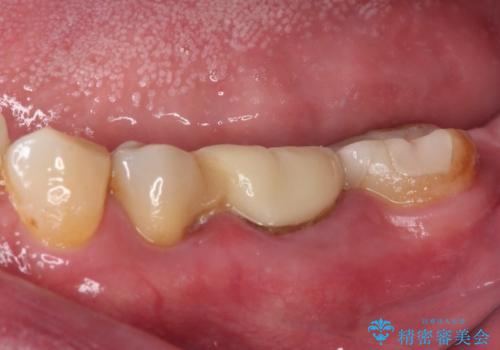

- 奥歯の詰め物が外れてしまったとのことで来院された患者様です。

レントゲン写真より、既に根管治療がされている歯であり、根尖部に骨透過像が認められました。

特に症状はありませんでしたが、根管治療を希望されたため、まずは根管治療を行うこととしました。

根管治療の際に、咬み合う上顎の銀歯が内側に入り込んでいることも気になるとのことであったため、部分矯正を行い、その後上下を同時に補綴治療することとしました。